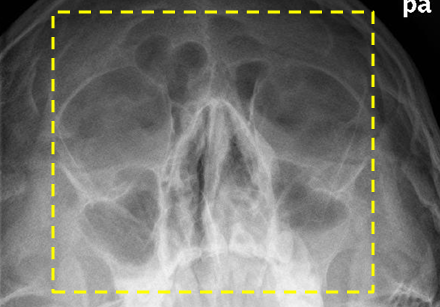

Positioning - PA Waters Nasal Bones

MML perp to IR, OML 37 from IR

bilateral outer canthus, supraorbital → upper lip edge

Critique - PA Waters Nasal Bones

Structures: nasal, frontonasal suture, maxillae, ant nasal spine